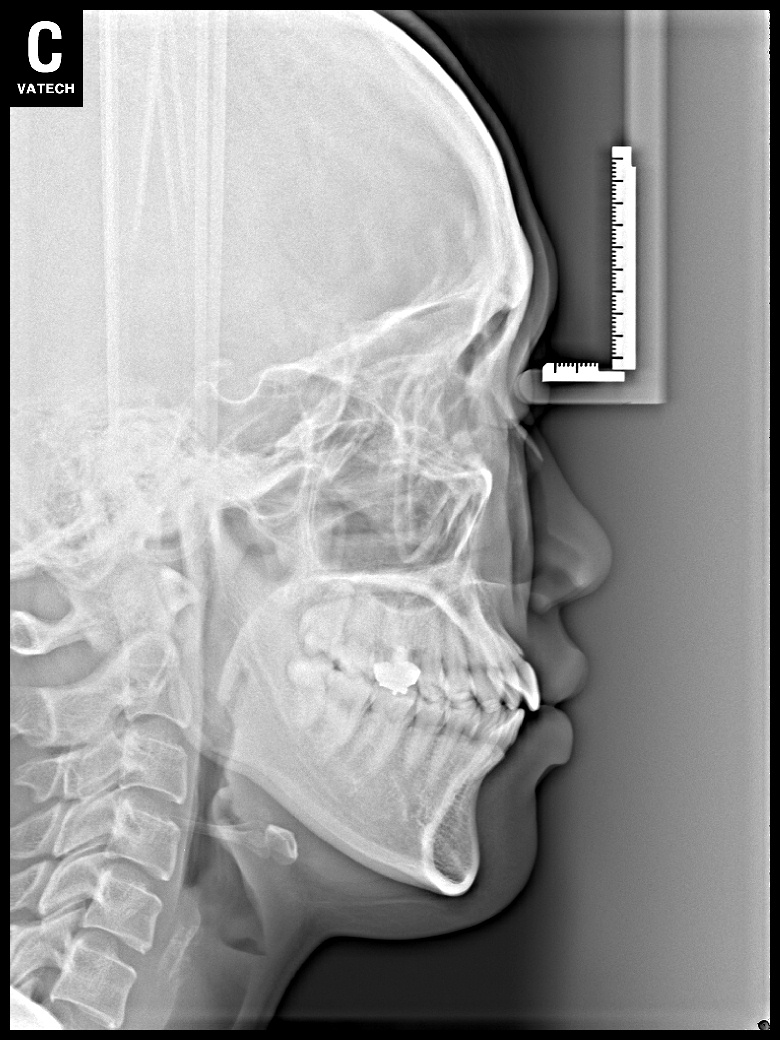

치료 후 사진입니다.